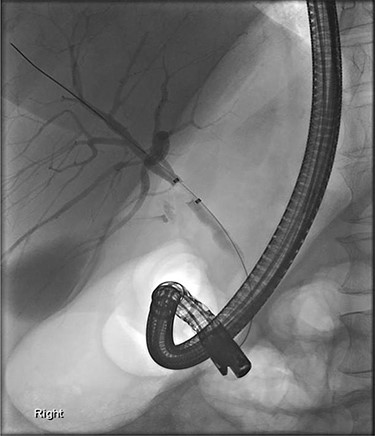

Further examination led to a diagnosis of DCBD with a separate left intra- and extrahepatic bile duct with ectopic drainage into the stomach. Magnetic resonance cholangiopancreatography (MRCP) revealed marked left intrahepatic duct (IHD) dilatation. The left IHDs were draining via an aberrant extra-hepatic bile duct into the pre-pyloric region. The left and right hepatic ducts did not communicate. It also demonstrated pancreatic divisum and multiple side branch intra-ductal papillary mucinous neoplasms (IPMN) (Fig. 3). Endoscopic retrograde cholangiopancreatography (ERCP) confirmed the MRCP findings but also revealed an intraluminal-filling defect in the left IHD (Figs 4 and 5).

ERCP: cannulation via the major papilla orifice into the CBD draining the right IHDs. There was no communication between the ACBD and the right IHDs.